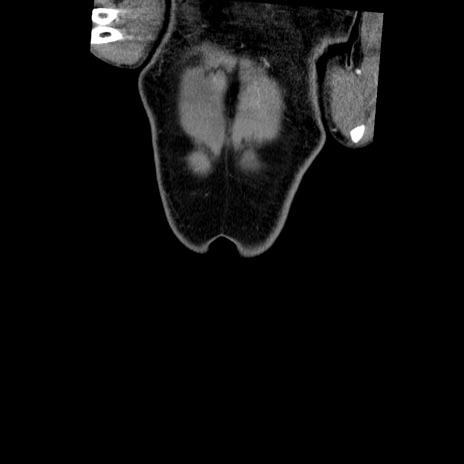

横断像